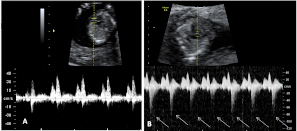

Ecografía Embarazo 2D y 3D Semana 12 - PRUEBAS DIAGNÓSTICAS